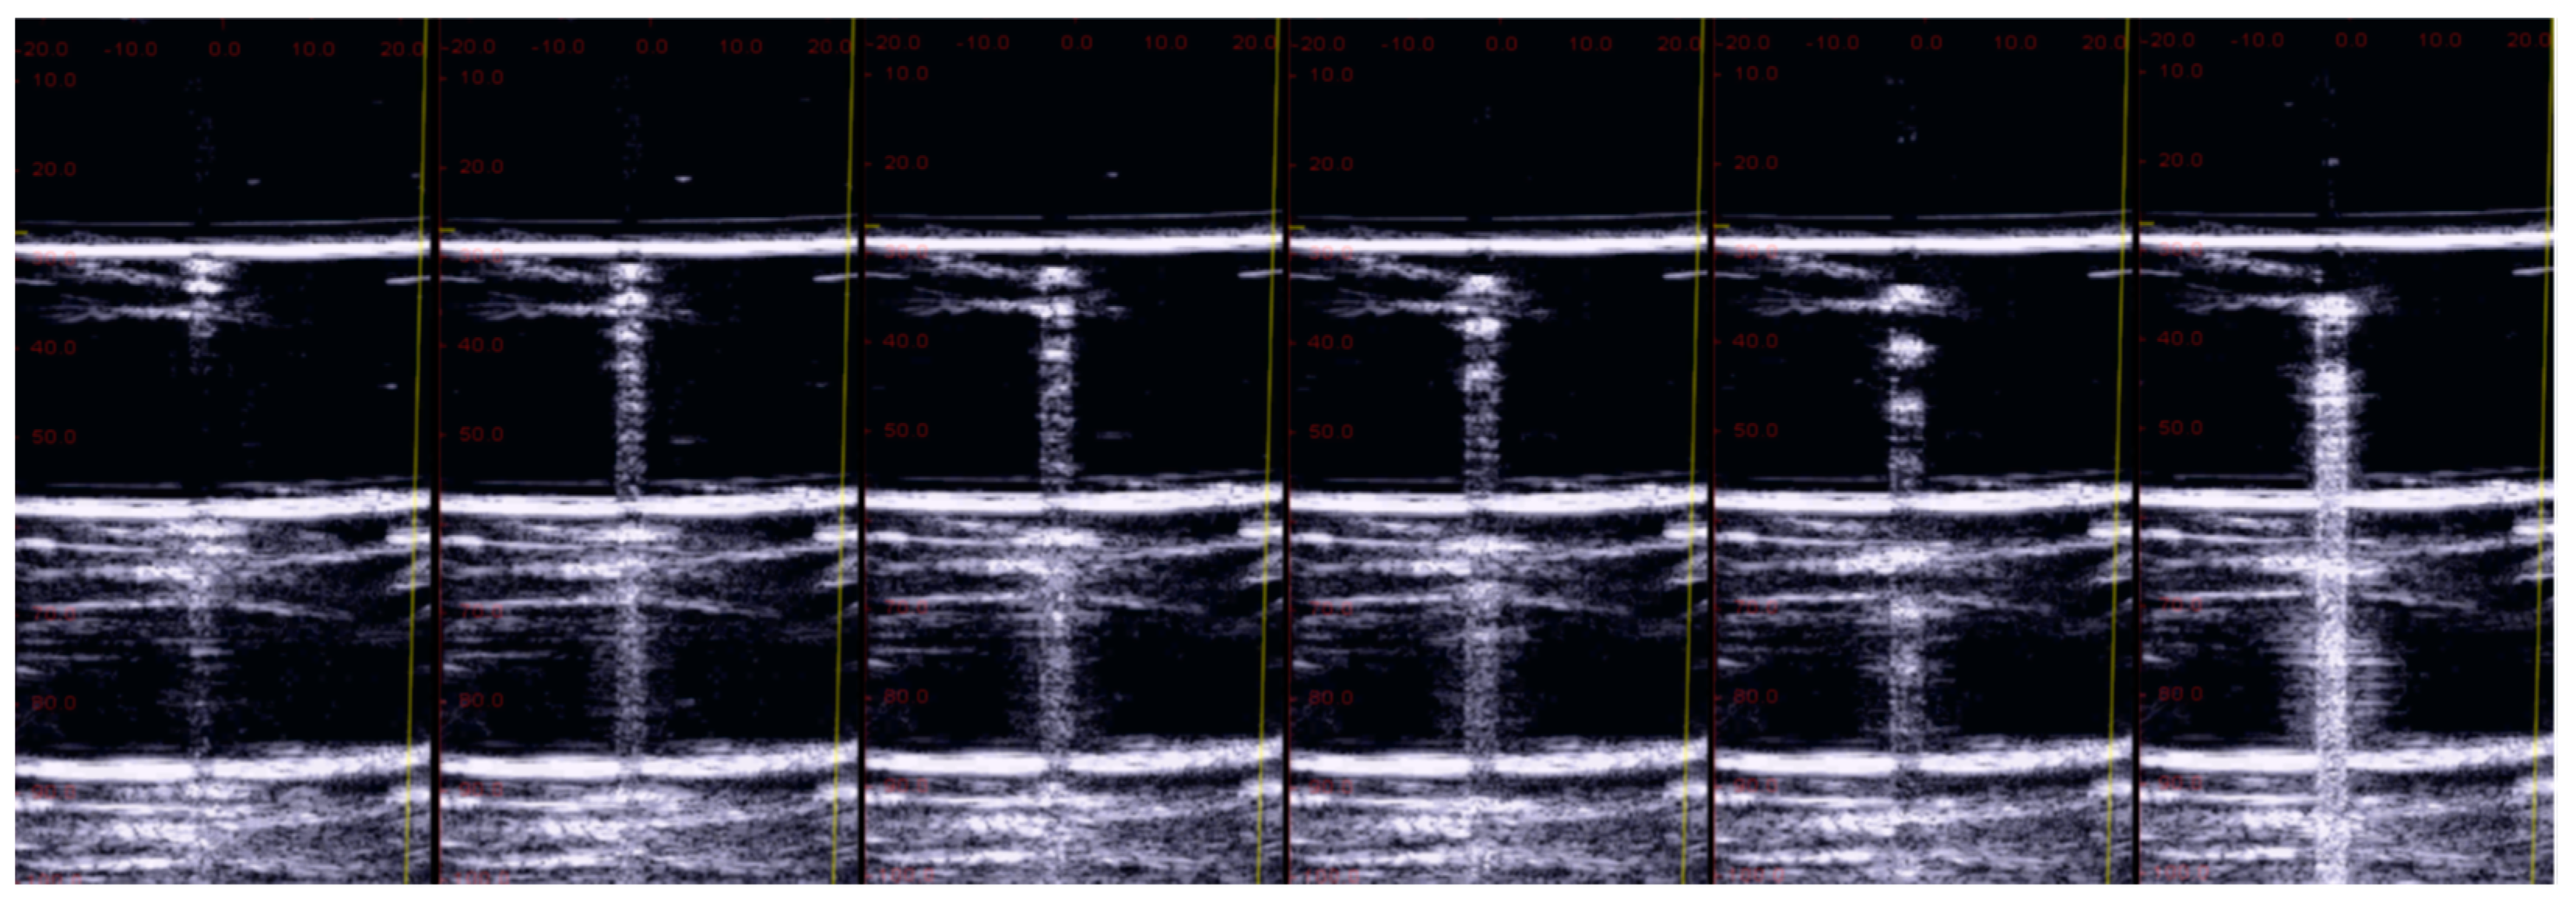

3.2. The Impact of Wrong Utilization of the Ultrasound Equipment